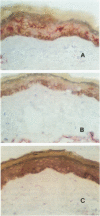

The LFA-1 integrin mediates its function in leukocyte intercellular interactions by recognition of at least one of its three identified counter-receptors, intercellular adhesion molecules 1 (ICAM-1), 2, and 3. The ICAM-1 molecule is expressed in an inducible-dependent manner by endothelial and epithelial cells, as well as by other cell types, including leukocytes. On the other hand, ICAM-2 is constitutively expressed mainly by endothelial cells. We have studied the tissue distribution of the ICAM-3 molecule by immunohistochemical staining of lymphoid and nonlymphoid organs. Only cells from the leukocyte lineage were found bearing the ICAM-3 antigen, showing a pattern of expression clearly distinct from those of ICAM-1 and ICAM-2. Interestingly, we have found that ICAM-3 is expressed by epidermal dendritic Langerhans cells as assessed by double immunostaining with antibodies specific for CD1. In contrast, staining of skin sections with anti-ICAM-1 and ICAM-2 antibodies showed an undetectable expression of these two molecules on Langerhans cells. However, CD1+ Langerhans cells localized in the paracortical area of dermatopathic lymph nodes expressed both ICAM-1 and ICAM-3 antigens. Our results indicate that ICAM-3 is the main LFA-1 counter-receptor in human resident epidermal Langerhans cells. ICAM-3 may have an important role in T-cell antigen stimulation driven by Langerhans cells during skin immune reactions.